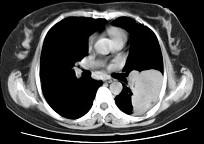

问题 女,52岁,左侧背痛1月,胸部CT如图,最可能的诊断为 ( )

选项 A.左肺中央型肺癌 B.左肺周围型肺癌 C.左肺感染 D.左肺炎性假瘤 E.肺隔离征

答案 D